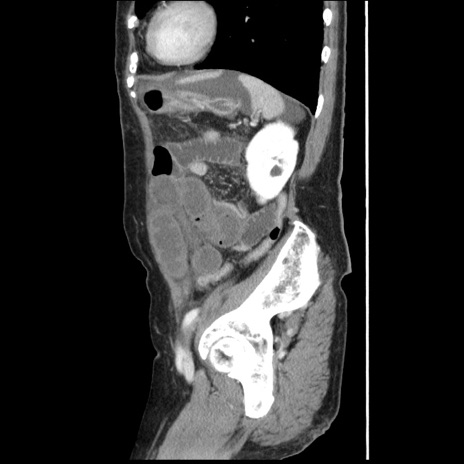

横断像

【症例】80歳代女性

【主訴】腹痛

【現病歴】8時間前から腹痛あり来院。

【既往歴】糖尿病、脂質異常症、子宮体癌にて子宮全摘術

【身体所見】意識清明・会話良好だが腹痛で苦悶様、全腹部にわたって反跳痛と圧痛あり

【データ】WBC 13600、CRP 0.14、LDH 224、CK 90